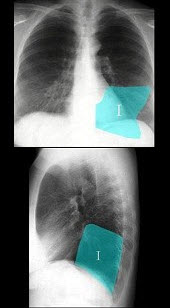

3、单项选择题

女,77岁,进行性吞咽困难月余,伴胸闷气短,腹胀。结合图像,最可能的诊断为()